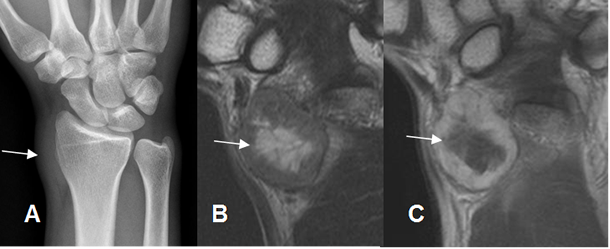

Fig 25. Lesión de tejidos blandos.

A: Rx AP. Prominencia de los tejidos blandos en la muñeca, sin compromiso óseo.

B: RM coronal en T2 y C: RM coronal en T1 con contraste. Imagen de tejidos blandos de predominio fibroso y necrosis central, que corresponde a schwanoma del nervio radial.